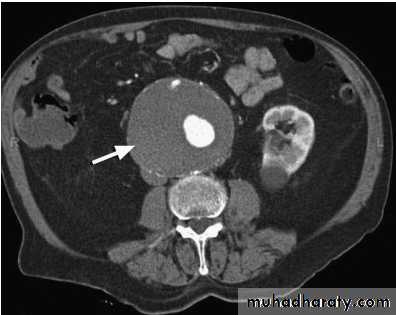

CT will provide much more accurate information about the size and extent of the aneurysm, the surrounding structures and whether there is any other intra-abdominal pathology, and is the standard pre-operative investigation; however, it is not suitable for surveillance.Arteriography is usually only indicated if there are concerns about associated lower limb, renal and/or visceral occlusive disease.

Three-dimensional abdominal CT showing abdominal aortic aneurysm

Contrast CT scan of a large, thrombus-filled abdominal